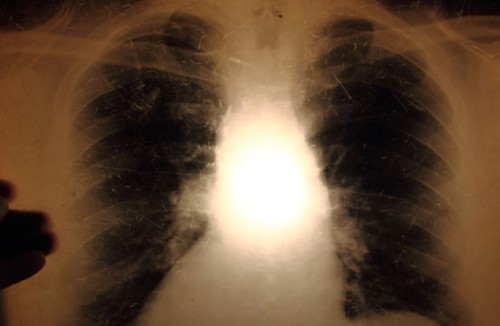

Examination for tuberculosis disease: If the screening for tuberculosis infection is positive, an X-ray examination of the lungs will be performed to detect any tuberculosis disease. A chest X-ray can also be used as a first examination if tuberculosis is suspected, or as part of a screening.